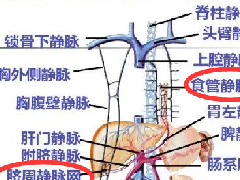

【影像表现】 钡灌肠:直肠与乙状结肠起始部可见不规则充盈缺损(图1箭头),肠管见偏心性狭窄;粘膜皱襞紊乱,纠集(图2、3箭头)。 CT:直肠壁不均匀增厚,见软组织影突入直肠腔内,增强扫描中度强化,周围脂肪间隙欠清楚,直肠后方可见肿大淋巴结(箭头)。肝脏体积增大,肝内密度欠均匀,可见多发弥漫不均匀低密度区,增强扫描病灶显示更加清楚,呈多发结节样低密度影,脾周及胆囊窝周围可见少量液性低密度影。

【讨论】大肠癌包括结肠癌(carcinoma of colon)及直肠癌(colorectal carcinoma),发生部位约半数以上位于直肠,20%位于乙状结肠,其次依次为盲肠、升结肠、降结肠、横结肠。发病年龄多在40~60岁,但30岁以下的青年大肠癌并不少见。临床表现:早期常表现为粪便隐血阳性;随后可出现排便习惯及粪便性状改变;腹痛;局部肿块及全身情况改变(右半结肠癌多见)。临床上习惯用Dukes分期:A期:癌局限于肠壁;B期:癌穿透浆膜;C期:有局部淋巴结转移;D期:有远处转移。

X线:增生型:主要表现为充盈缺损,充盈缺损周边的的粘膜破坏中断或见小溃疡。气钡双重造影可显示肿块的轮廓。溃疡型:主要表现为腔内突起的龛影和“半月征”。浸润型:主要沿肠壁环形生长,使肠壁增厚,肠腔狭窄,可见狭窄段粘膜呈锯齿状。混合型:常有两种以上的表现混合存在。